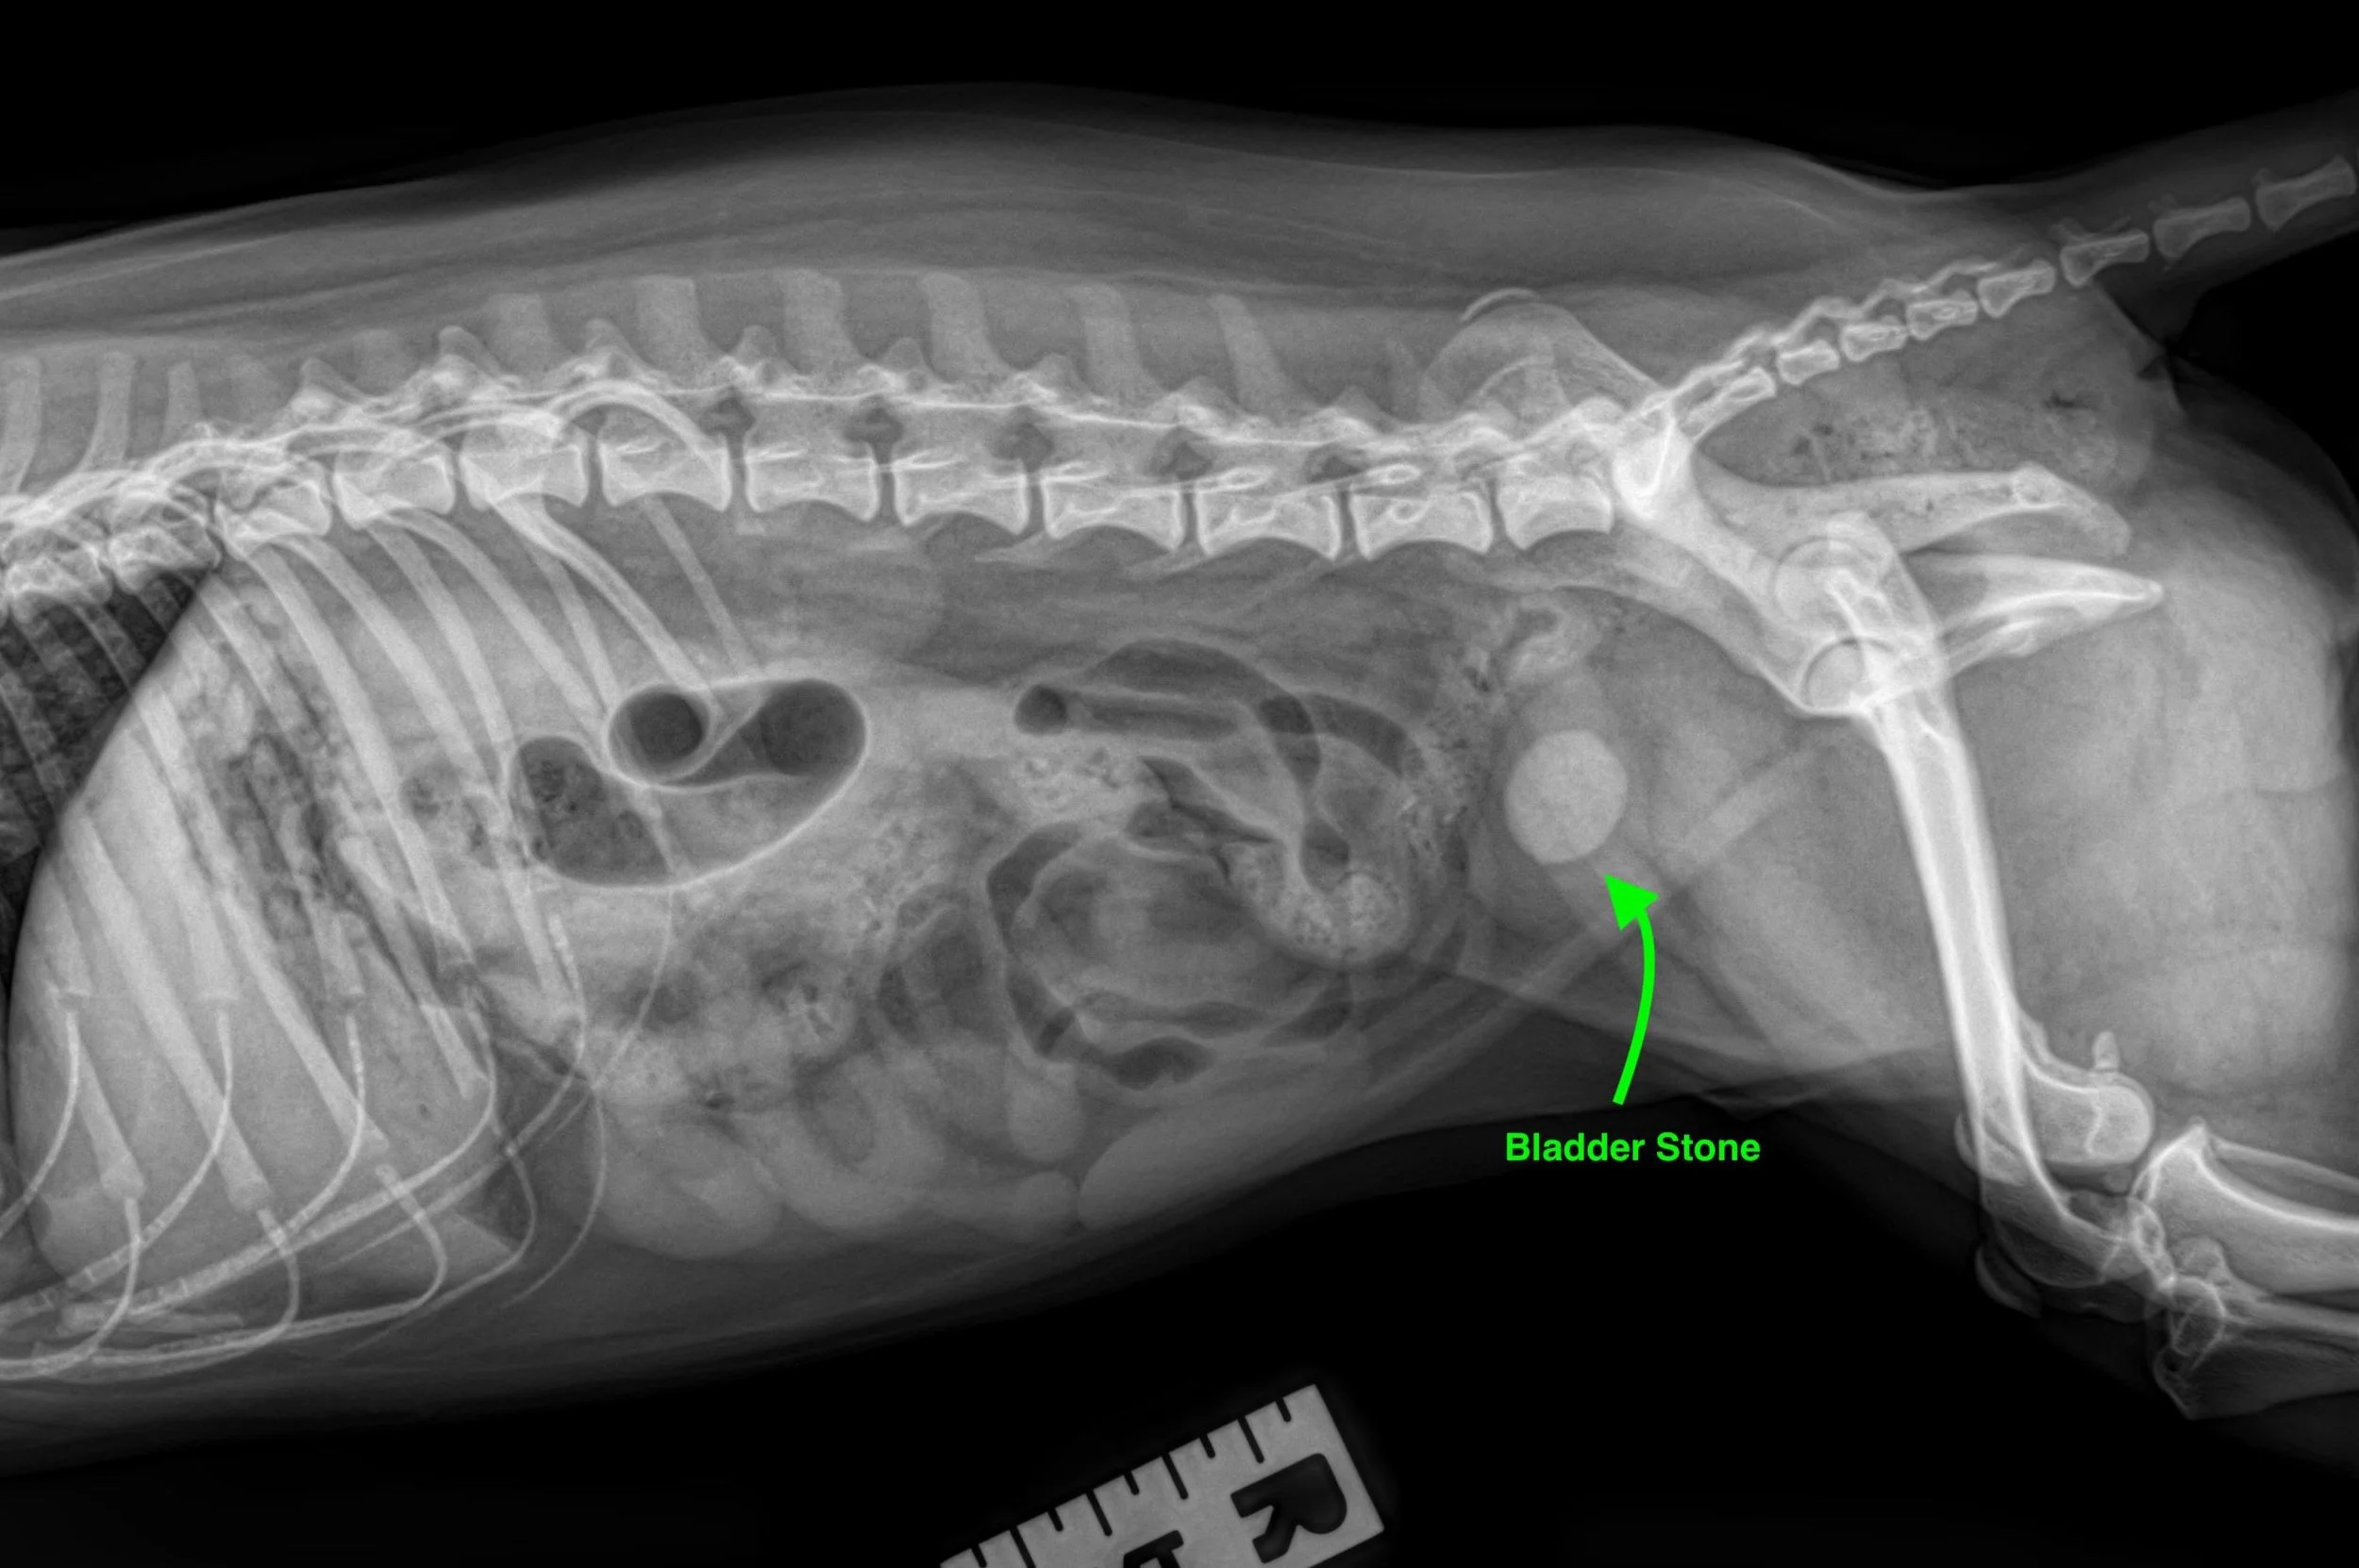

Some large stones can be felt on physical examination; however, most pets need to have an x-ray or ultrasound of the bladder to see the stone.  A urinalysis and culture of the urine are often performed to determine the crystal type of stone and other related concerns. After removal, the stones will be sent for mineral analysis.

Figure 1:  Radiograph of a dog with a large bladder stone.